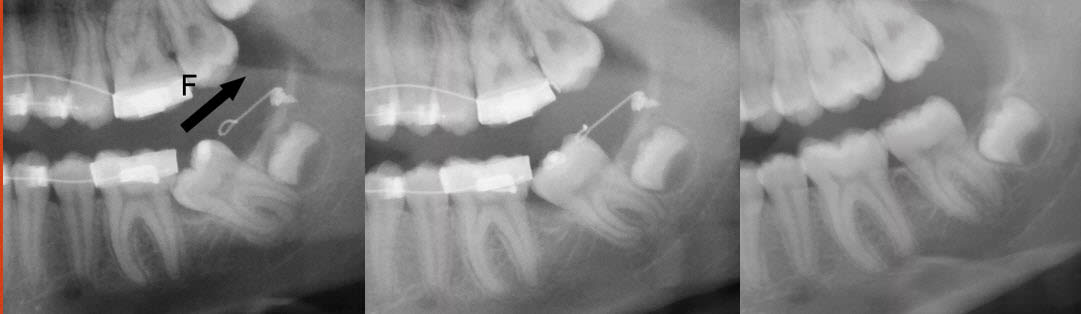

Je ne suis absolument pas d'accord avec l'extraction !

Cette dent est à redresser, cela ne devrait même pas se discuter.

Quand à parler de "galère", il suffit d'employer la bonne technique...

Un CT8 (ou même un simple CTO comme sur les photos jointes car elle n'est qu'enclavée) ) est le système de choix.

Daniel

Il n'est pas tant question de technique ou de faisabilité que d'intérêt final. Ce cas n'a rien à voir avec celui que tu présentes en panoramique, l'espace disponible n'est pas du tout le même.

Le CT8 est un très bel outil, élégant et efficace je trouve, que j'aimerais mettre en place au cabinet, mais il a ses indications et ne va pas miraculeusement créer de l'espace en distal... Ca me rappelle la petite phrase d'un de mes profs de fac, qui nous avait mis en garde en disant un quelque chose de ce genre : "attention, quand on a un marteau dans la main, on voit des clous partout !". J''appelle ça aussi le syndrôme Ikea : quand on rentre en magasin et qu'on récupère un ruban mètre, on a subitement envie de TOUT mesurer !

... sauf que vous oubliez que la branche montante est en vestibulaire par rapport à l'arcade.

Une radio panoramique ne me paraît pas suffisante dans ce cas-ci pour décider de supprimer 4 molaires dont 3 sont déjà sur l'arcade.